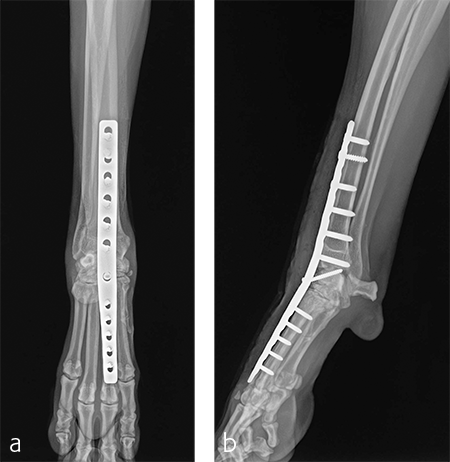

Postoperative radiographs revealed proper joint orientation and compression of the multiple antebrachiocarpal joint levels (Fig 5). Implant placement was considered excellent.

A custom fiberglass palmar splint was applied from the paw to just distal to the elbow after surgery. The splint was used for 4 weeks followed by a soft padded bandage for 4 weeks. Bandage changes were performed weekly. Activity was restricted to leash walks only for 12 weeks postoperatively. Radiographic examination 8 weeks after surgery revealed early healing of the pancarpal arthrodesis and stable implants. No complications were noted (Fig 6).